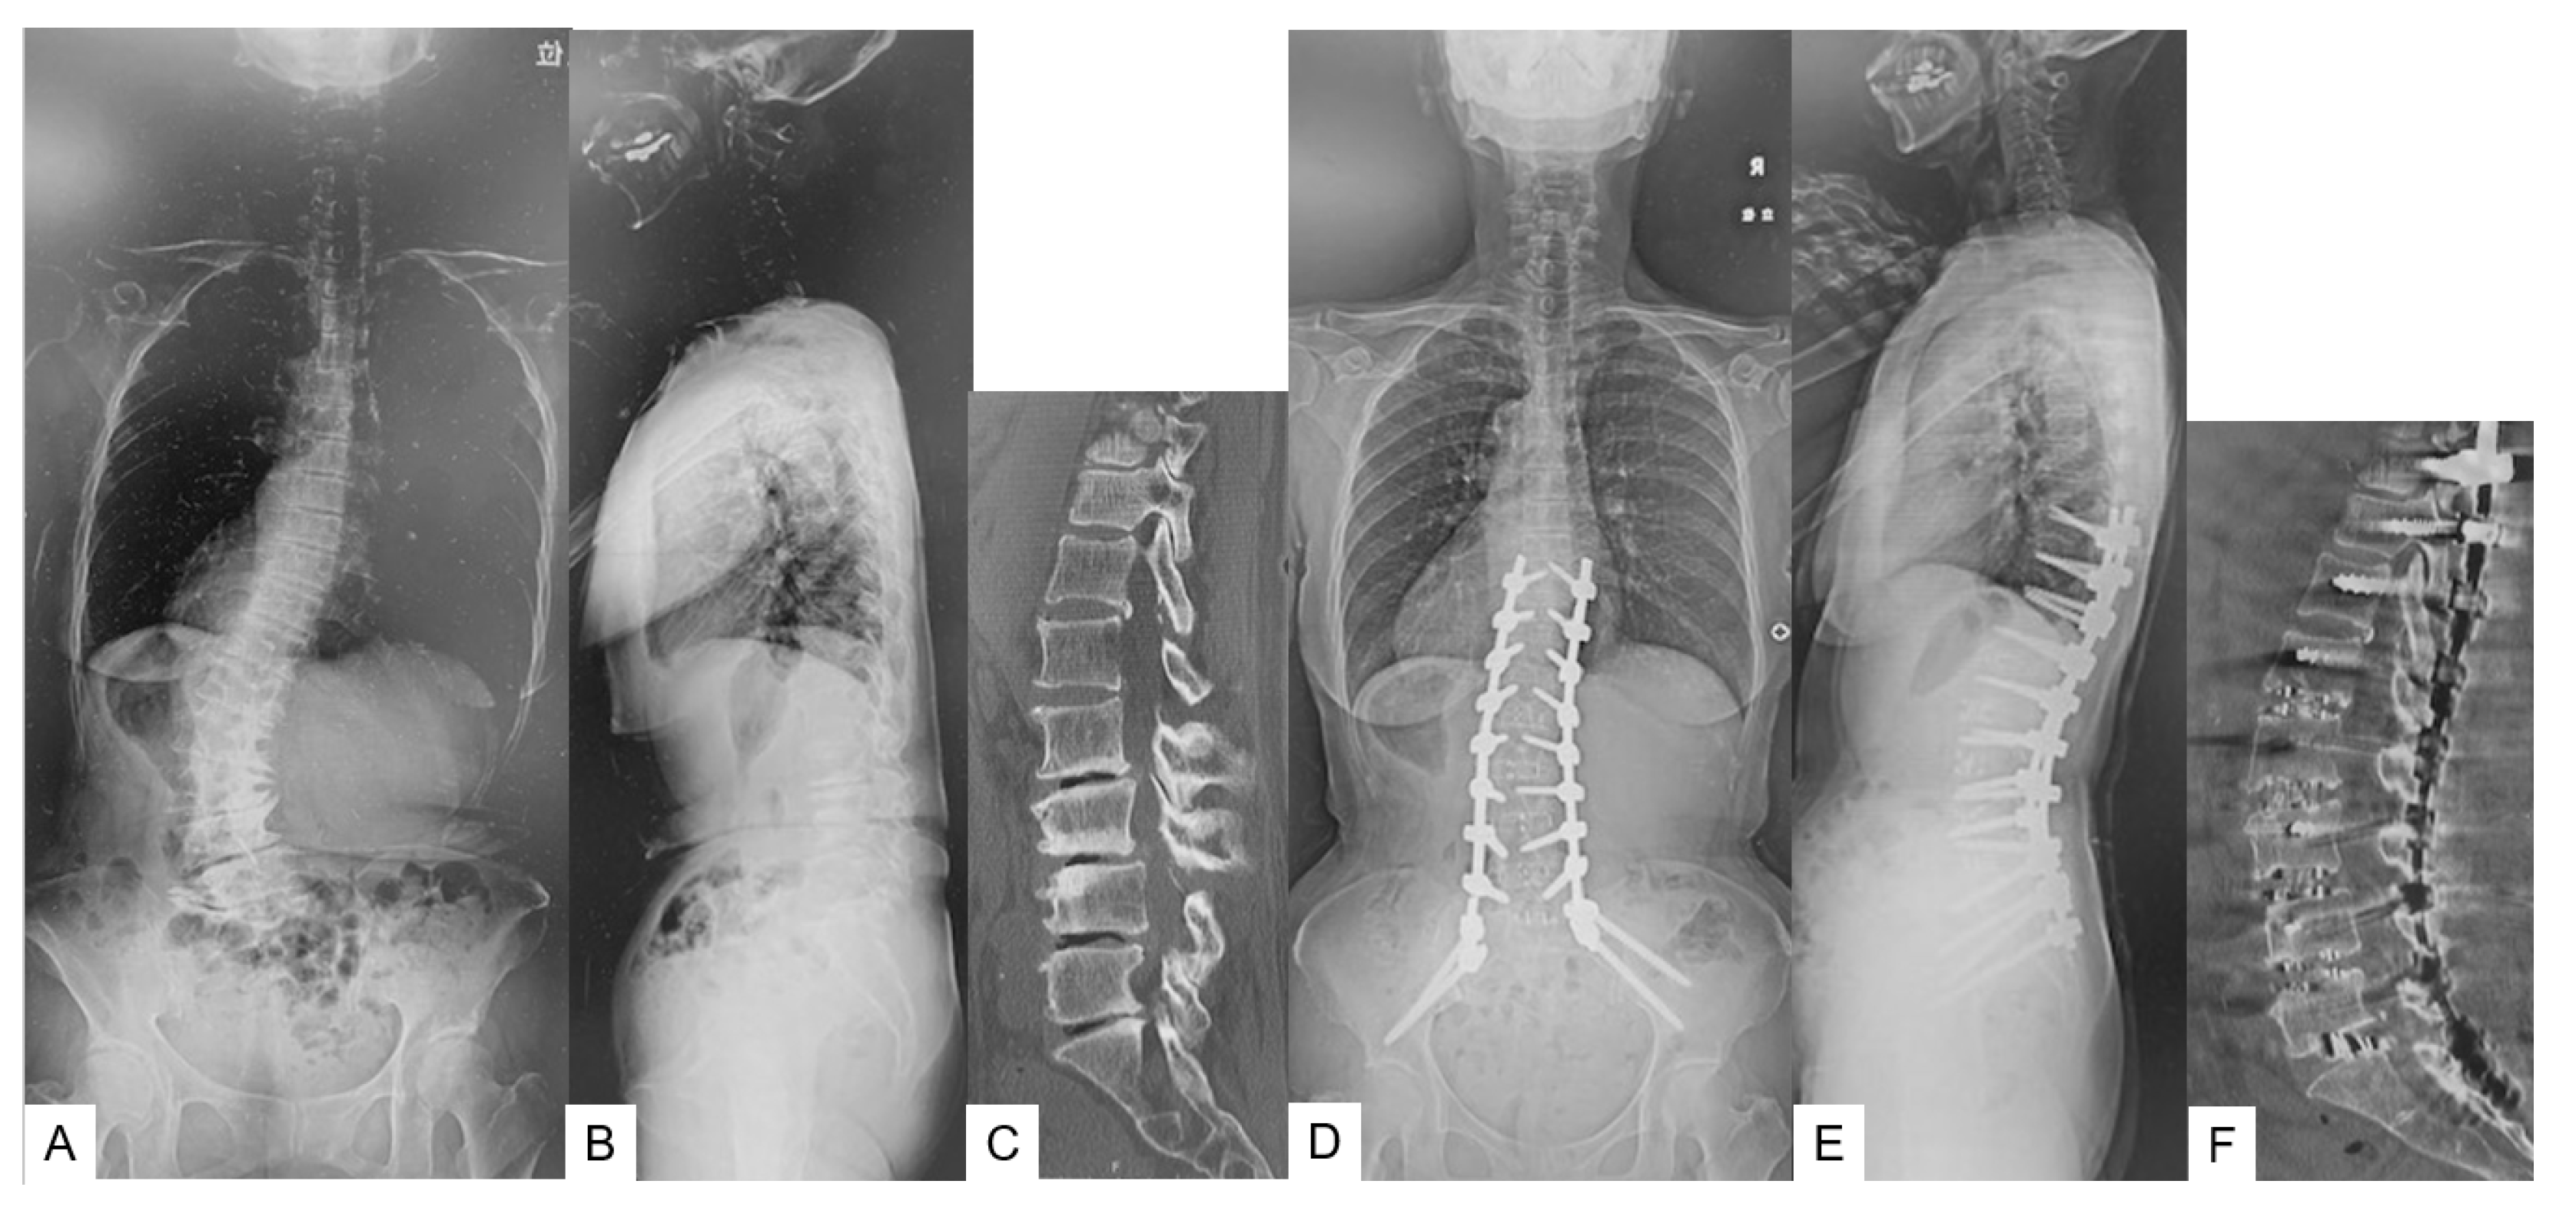

- Case 2 72-year-old woman, adult spinal deformity